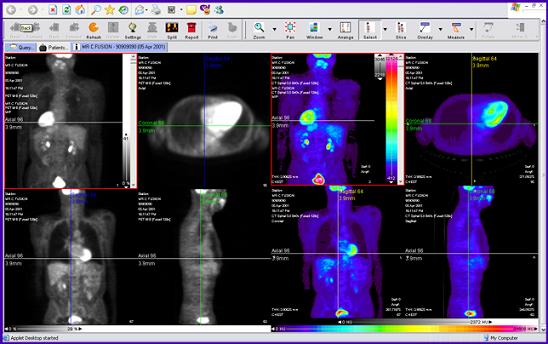

PET CT ile tek seansta hem hücrelerin metabolik fonksiyonu hem de anatomisi 3 boyutlu olarak görüntülenirken ayrıntılı ve kesin bilgiler elde ediliyor. Bu şekilde, hastanın durumu hakkında en iyi bilgi elde edilebiliyor ve özellikle kanser hastalarında en iyi tedavi şekline karar verilebiliyor. Kanser hastanemizde bulunan PET CT cihazı ile küçük tümörler bile kolaylıkla tespit edilebiliyor.

PET tarayıcılar tümör odaklarının metabolizmasını ve küçük tümörleri belirleyebilir. Ancak CT bileşeni olmadan bunların tam olarak nerede olduğunu göstermek konusunda yetersiz kalır. Ayrıca, PET CT cihazları PET cihazlarına göre belirgin olarak hızlıdır ve kapalı yer korkusu olan hastalar için geniş olarak tasarlanmıştır.

• Mükemmel görüntü kalitesine ve çözünürlüğe ulaşılıyor.